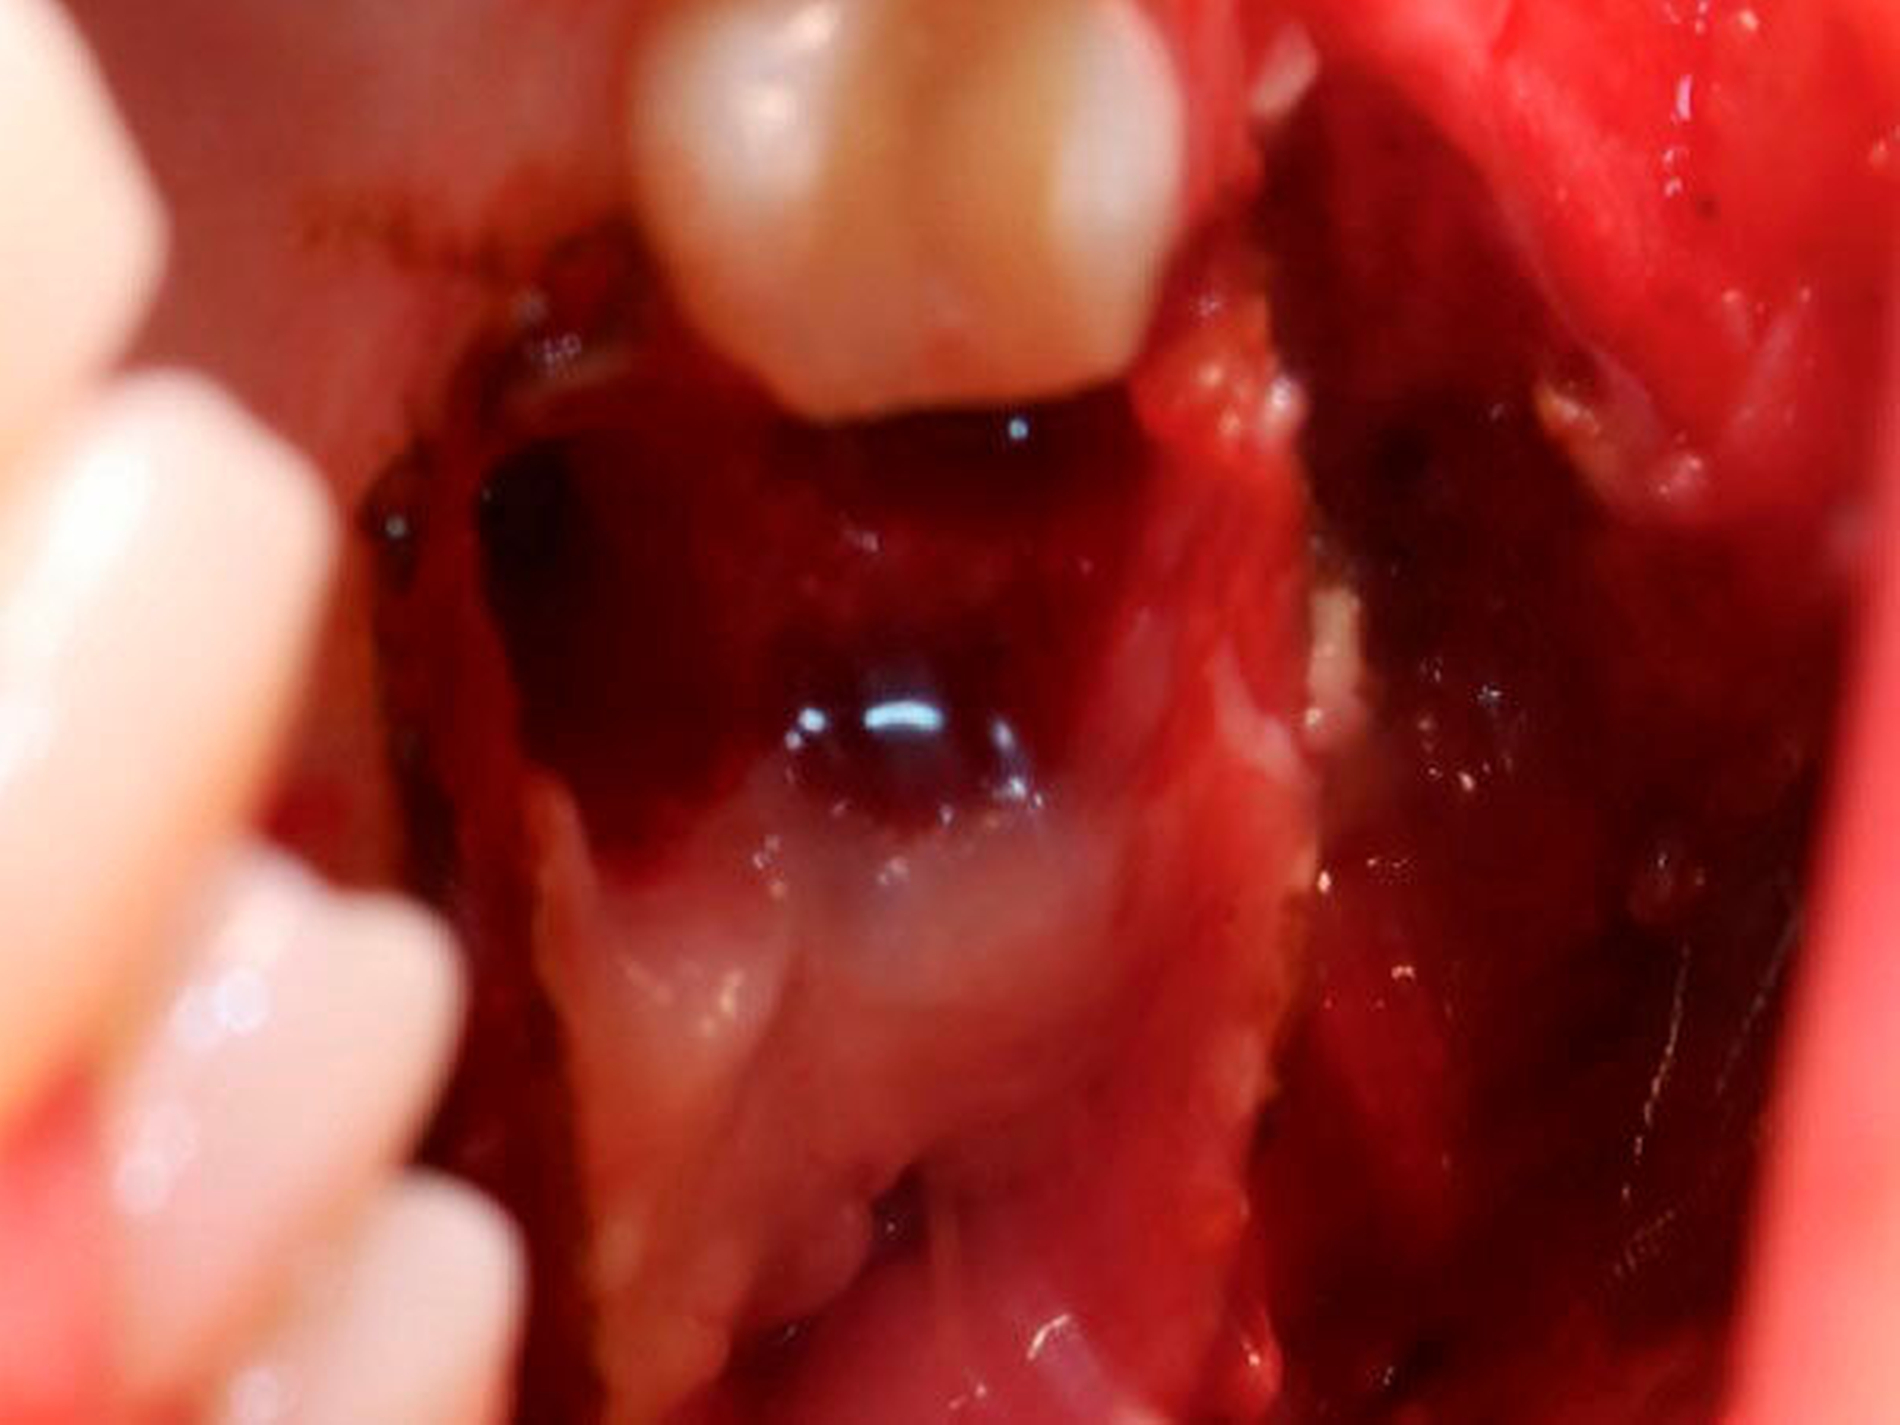

Die Allgemein- und Familienanamnese der Patientin war bis auf eine medikamentös eingestellte Hypothyreose unauffällig. Extraoral bestand kein auffälliger Befund, insbesondere keine Druckdolenz oder Nervdefizit über der Kieferhöhle links. In Regio 27 zeigte sich eine Mund-Antrum-Verbindung nach frustranem Deckungsversuch, aus der sich seröse Flüssigkeit entleerte (Abbildung 2). Der Zahn 26 reagierte negativ auf Perkussion und war avital. Nach sorgfältiger Aufklärung erfolgte die Resektion des Befunds in Intubationsnarkose. Folgend auf die Extraktion des Zahnes 26 (Abbildung 3) wurde eine Kastenresektion der linken Maxilla von distal des Zahnes 25 bis in den Tuberbereich bei makroskopischem Einhalten eines Sicherheitsabstands von 0,5 cm durchgeführt. Das narbig anmutende Gewebe in der Kieferhöhle wurde ausgeschält und en bloc mit dem Oberkieferresektat entfernt (Abbildung 4). Der Knochen wurde hier belassen, da er klinisch und radiologisch nicht infiltriert war.

Der Defekt wurde mit einer lokalen Lappenplastik gedeckt (Abbildung 5), eine vorab angefertigte Verbandsplatte zum Wundschutz eingegliedert. Die abschließende histologische Auswertung (Abbildung 6) bestätigte, dass es sich bei dem kompletten Resektat um das bereits ex domo vor-diagnostizierte, teils plexiforme Ameloblastom handelte. Aufgrund der Größe des Tumors erfolgte ein Staging mittels CT-Thorax und Abdomen, das jedoch keinen Nachweis einer Metastasierung erbrachte. Bei mikroskopisch knappen Sicherheitsabständen nach palatinal sowie an der Nasenscheidewand und zur Orbita hin wurde die Patientin über ein differenzial-therapeutisches Vorgehen mit radikal-chirurgischem Vorgehen versus engmaschige klinische und radiologische Nachkontrollen aufgeklärt. Die Patientin entschied sich nach eingehender Aufklärung für die engmaschigen Nachkontrollen. Eine ossäre Rekonstruktion (Abbildung 7) wird derzeit von der Patientin nicht gewünscht.